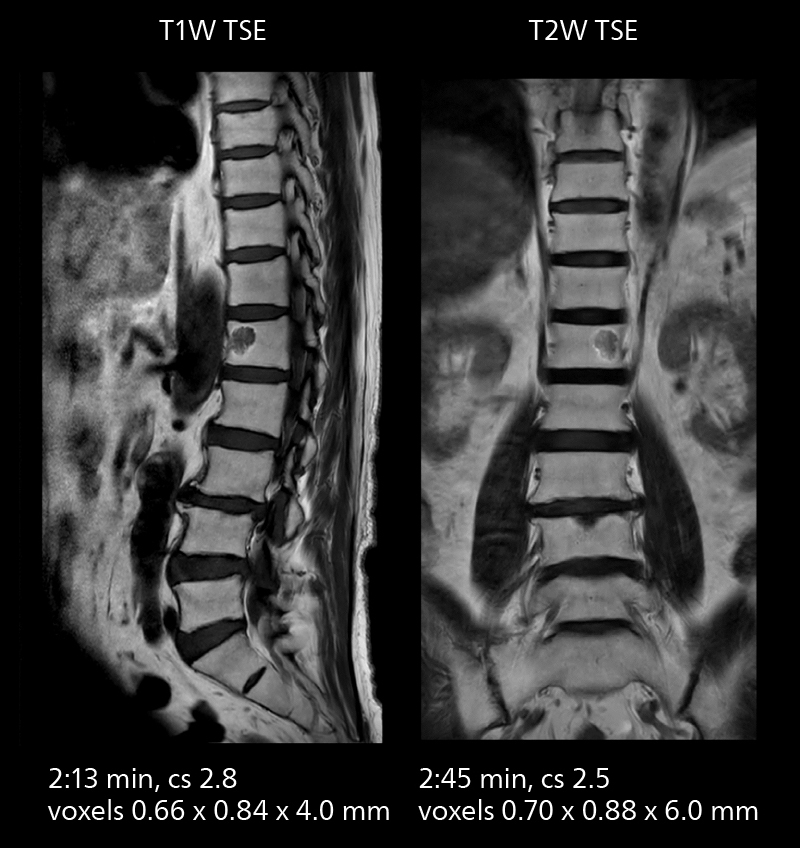

Crisp images are obtained with high resolution and short scan times using Elition X. A cyst can be seen.